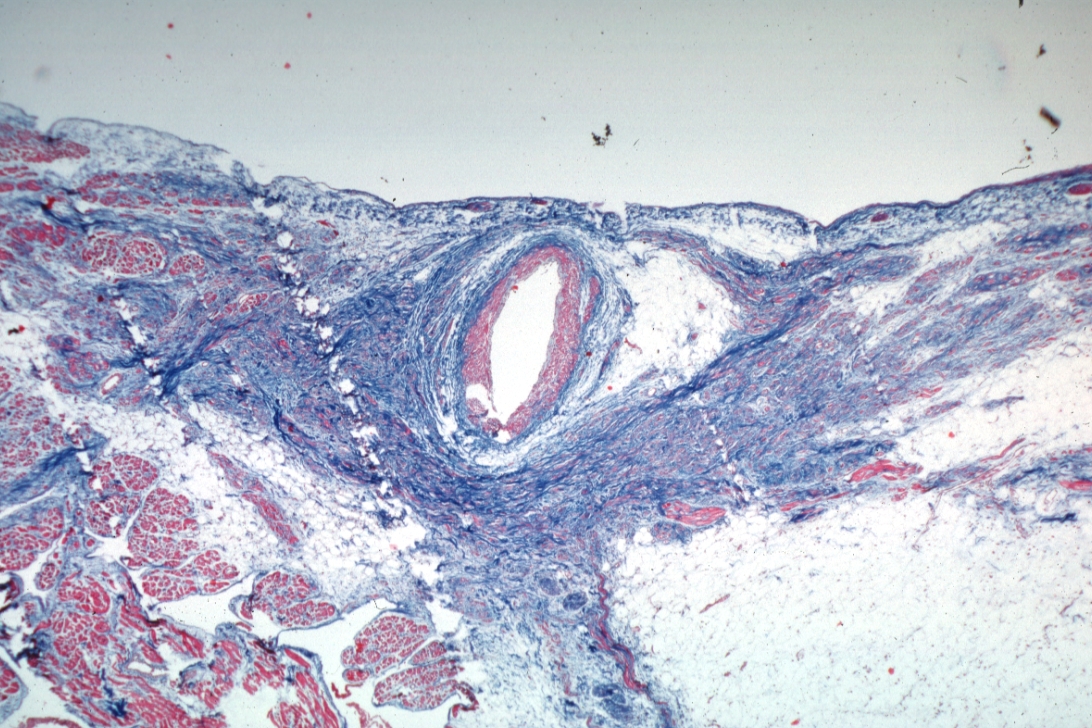

HISTOLOGY: CARDIOVASCULAR: HEART: Sinus Node Fibrosis: Micro low mag trichrome this shows more conducting tissue than and quite good photo with normal sinus node artery